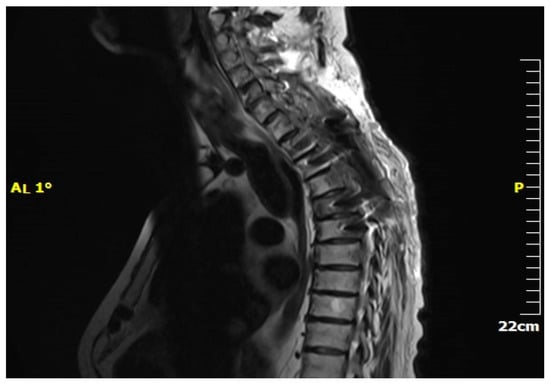

3.4. Diagnostic Evaluation